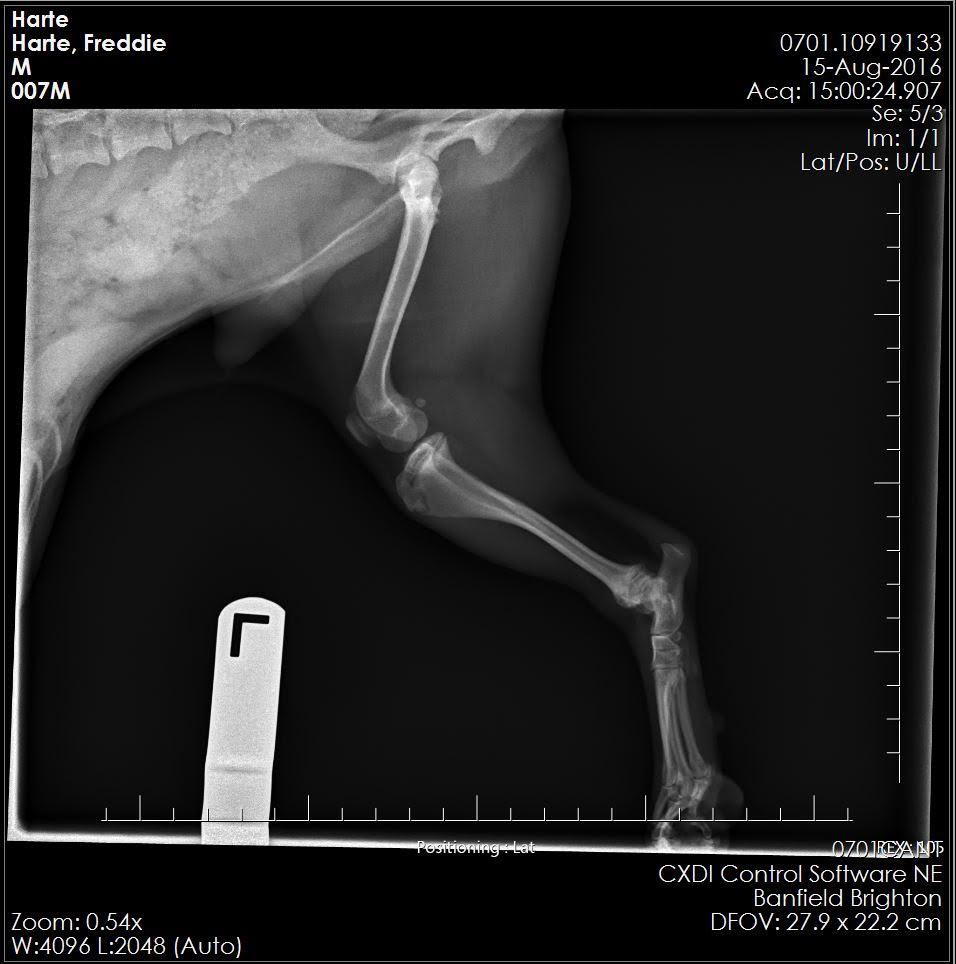

these are X-rays of my 1.5-year-old Yorkie Shih Tzu Mix or a Shorkie-Zu, his name is Freddie. He sometimes limps but mostly he doesn’t. He has as you can see muscle built up on his left leg. It seems like he limps on both of them when he does but he doesn't do it consistently. He had a cryptic orchid that has been removed. I have been told they don't know what is wrong with him.

I'm sorry to hear about Freddie Harte's limping. I am not seeing any obvious defects on this x-ray. The challenge is that the findings on exam are extremely important in trying to diagnose orthopedic issues; it would help to know if Freddie has proprioceptive deficits in his hind end, decreased range of motion, muscle atrophy, medial buttressing, etc as well as trying to localize any pain that may be contributing to his limping - all of this information would be combined with findings on x-ray to try to reach a diagnosis. Small dogs such as Shih Tzus are prone to luxating patellas, which may not always be evident on an x-ray but would be detected on exam. Did your vet discuss the option of referral to a specialist for a more concrete answer? I'm happy to give you my input on the x-ray - but referral to an orthopedic specialist who will be able to put their hands on your dog, as well as look at these x-rays, will give you much more beneficial input. I know its frustrating to have a chronically limping dog without an answer! I hope this helps!